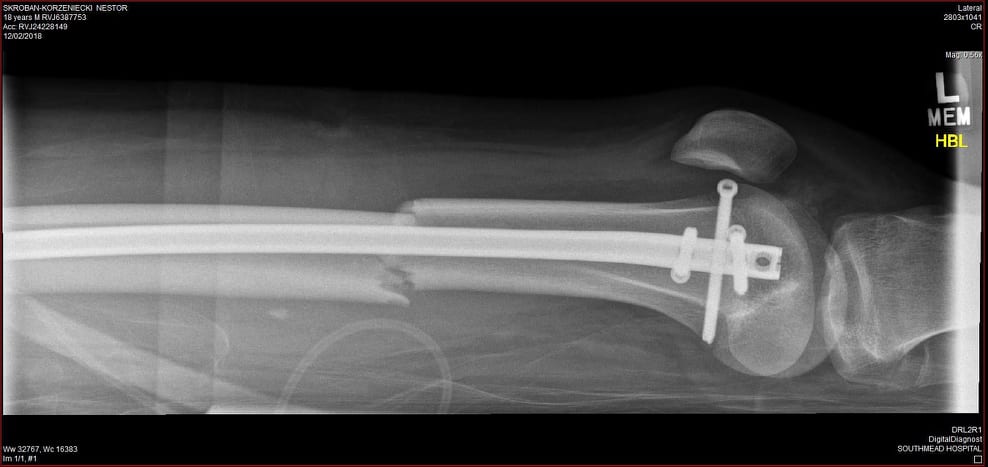

I received a place in Gloucestershire College, Coleford Campus, where I studied Art and Design Level 2 for a year before moving on to Level 3 for two years during which, on 2 February 2018, I was involved in a road traffic collision on my moped with a 73-year-old woman in her car. This resolted in a metal rod to be put in the broken left femur, a screw in the top part near the hip and three screws in the knee.

I spent three weeks in Southmead Hospital, including 9 days in a medically induced coma, in Bristol and a week in Gloucestershire Royal Hospital. During that time, my art and design teacher and general amazing person – Katie, set up a fundraiser with the help of my entire class. My parents bought a painting in that fundraiser that Katie did and my parents still have it framed up in the kitchen.